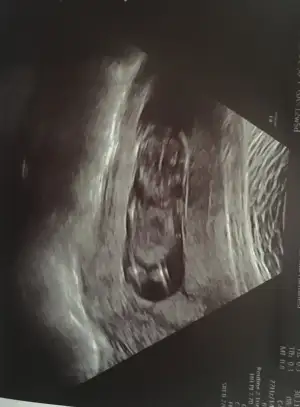

Ne dediler peki,kemik yapısından da çok net bulunabiliyorlar

İlk doktor 11+4 te açı bulamamış kızı andırıyor demişti. Bugün başka doktora gittim 12+5 ti erkek dedi çıkıntı var ama erken daha dedi bilmiyorum yani farklı dediler

Bana nub tahmini yok mu :)

Benim de aynı sonuç çıktı ense kalınlığı. Ama doktorum cinsiyet konusunda bir yorum yapmadı maalesef :confused:

Aynı dertten bende de var da o yüzden sordum,Turgut Özal Hastanesi var burda önceden özel hastaneydi,sonradan devlete geçti,ama hastanenin içi on numara filan,ben de oraya Gebe Okuluna gittim ,gitmişken bir de bebeğimi kontrol ettiriyim dedim,ultrasyon ile baktılar,ultrasyon kağıdı verince de şaşırdım hatta ,vermiyorlar zannediyordum.Keşke almasaydım ,bebeğin nerde olduğunu bile anlayamadım ,anlayan varsa bana da desin :KK70:

kafayı ve ayakları gördüm sanki :KK70: